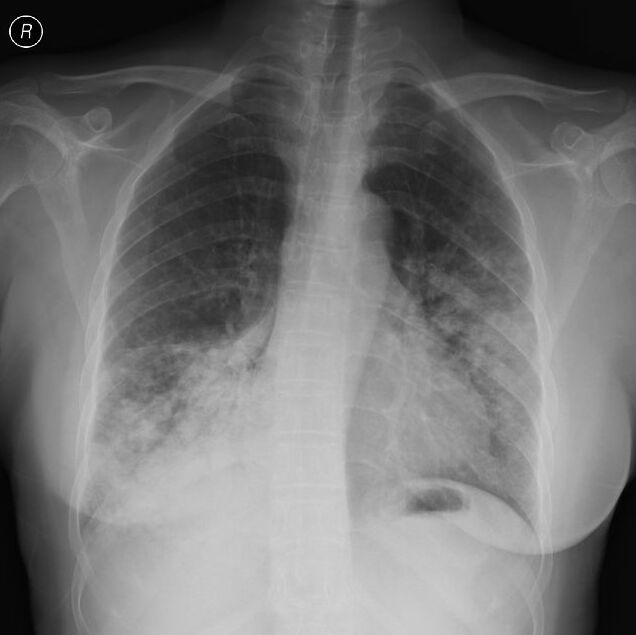

这是一位62岁的小老太,咳嗽咳痰伴低热一个月,伴有白色粘液痰。

胸部平片示重症肺炎表现(2012-7-23),临床伴有II型呼吸衰竭表现。